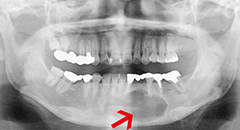

(1)歯根嚢胞

歯根の先に発生した膿の入った袋状の組織は歯根嚢胞と言います。

長期にわたる歯髄(歯の神経)の炎症や壊死(歯髄が腐った状態)などが原因です。嚢胞部の骨は炎症によって溶けて消失しており、根管治療(歯髄の治療)だけでは治癒が困難な状態です。嚢胞の除去と同時に細菌等が付着した根の先を切除することによって、抜歯を行わず歯を残すことを目的とした手術を行います。歯根嚢胞が放置された場合、周りの骨を溶かしながら嚢胞が増大し、隣在歯の障害(歯髄壊死等)、顎骨の膨隆などを生じます。嚢胞の増大はゆっくりで、1~2か月での変化はあまりないと思われますが、1年以上経過すると増大の可能性が高くなります。そのため歯根嚢胞が現在より、さらに増大する前に手術を行うことが必要です。

(2)顎骨嚢胞

顎の骨の中に生じる液状の内容物を含む袋状の疾患です。多くの場合、埋伏している歯に関連して発生します。発育は緩慢ですが、痛みなどの症状なく増大することが多く、発見された時にはかなり大きくなっている場合もあります。